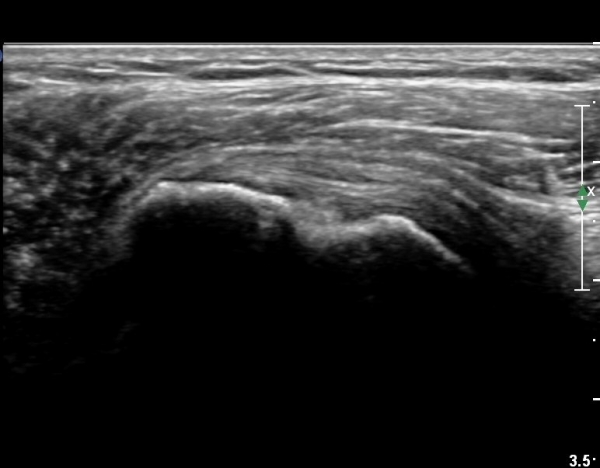

ŽÃËÀÚ¸¦ Á¶±Ý ¾Æ·¡·Î À̵¿ÇÏ¿© À̵ιڱٰÇÀÇ È¾´Ü¸é°Ë»ç¿¡¼­ ÀÌµÎ¹Ú±Ù°Ç ÁÖÀ§ ¼ö¾×Àú·ù°¡ °üÂûµÈ´Ù(»çÁø 3, 4).

À̴ Ȱ¾×¸·¿°Áõ ¼Ò°ßÀ¸·Î Ãæµ¹ÁõÈıº ¶Ç´Â ȸÀü±Ù°³ ÆÄ¿­ ½Ã ÈçÈ÷ °üÂûµÇ´Â

¼Ò°ßÀÌ´Ù.